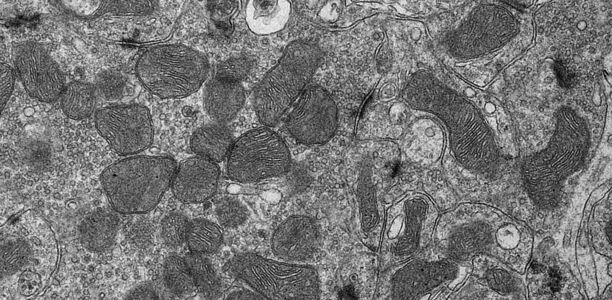

Unser Körper benötigt Energie – für jeden Stoffwechselprozess, jede Bewegung und zum Atmen. Diese Energie wird in winzigen Bestandteilen unserer Körperzellen hergestellt, den Mitochondrien. Im Gegensatz zu anderen Zellbestandteilen besitzen Mitochondrien ein eigenes Erbgut, die mitochondriale DNA. In bestimmten Situationen geben Mitochondrien ihre DNA jedoch in das Zellinnere ab, was eine Reaktion des zelleigenen Immunsystems hervorruft und mit diversen Krankheiten und dem Alterungsprozess in Verbindung gebracht wird. Die Gründe für die Freisetzung der mitochondrialen DNA sind bislang nicht bekannt.

Um die Frage zu beantworten, wann Mitochondrien ihre DNA abgeben, haben sich Forschende am Max-Planck-Institut für Biologie des Alterns auf das mitochondriale Protein YME1L konzentriert, das seinen Namen Hefemutanten verdankt, die ihre mitochondriale DNA freisetzen – yeast mitochondrial escape 1. „In Zellen ohne YME1L, haben wir die Abgabe der mitochondrialen DNA in das Zellinnere und eine damit zusammenhängende Immunreaktion in den Zellen beobachtet“, sagt Thomas MacVicar, einer der beiden Erstautoren der Studie. Bei genaueren Untersuchungen wurde ein direkter Zusammenhang zu den Bausteinen der DNA festgestellt. „Fehlt den Zellen YME1L, kommt es zu einem Mangel an DNA-Bausteinen im Zellinneren“, schildert Thomas MacVicar. „Dieser Mangel löst die Freisetzung der mitochondrialen DNA aus, was wiederum eine Entzündungsreaktion in der Zelle hervorruft: die Zelle löst ähnliche Entzündungsreaktionen aus wie bei einer bakteriellen oder viralen Infektion. Geben wir den Zellen DNA-Bausteine von außen hinzu, stoppt das auch die Entzündung.“